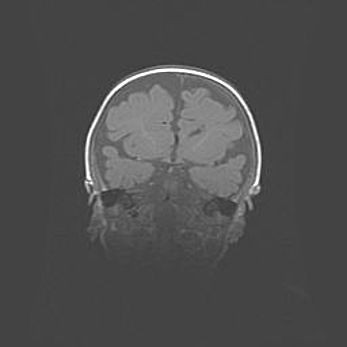

Наружная гидроцефалия с возможной атрофией височных областей.

Возраст: 28 дней

Вес: 3670 г

Пол: мужской

Окружность головы: 38 см

Срок гестации: 40 недель

Гидроцефалия головного мозга у новорожденных – это заболевание, которое характеризуется скоплением избыточного количества спинномозговой жидкости в желудочковой системе головного мозга в результате затруднения её перемещения от места выработки к месту поглощения в кровеносную систему или вследствие нарушения абсорбции. При открытой наружной форме гидроцефалии у новорожденных расширяются и переполняются субарахноидные пространства.

При нормотензивных  формах,  которые,  как  правило,  являются  следствием  перенесенных ишемических  повреждений  паренхимы  мозга,  возможно  сочетание микроцефалии  с нормотензивной гидроцефалией. В основе данных изменений лежит атрофия больших полушарий с преимущественной  локализацией  в  лобно-височных  областях.